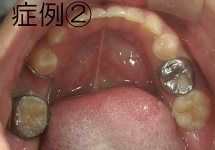

リンガルアーチ

主に奥歯の6番目の傾斜を立てなおしたり、ねじれた歯をもとに戻す際に使用する装置です。この症例の場合、舌側へ傾斜していた大臼歯が、装置の力で正常な位置まで起き上がりました。